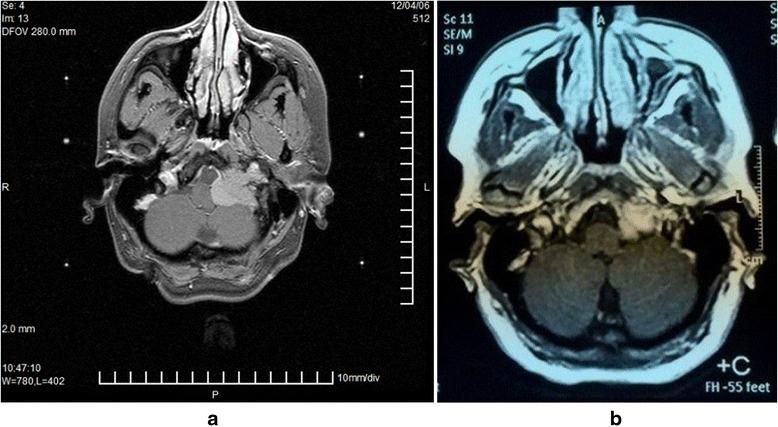

球瘤是罕见的颅底生长缓慢、血管丰富的肿瘤,常累及关键的神经血管结构,且诊断延迟很常见。手术切除很少能做到根治,且通常伴有发病率或死亡率。伽玛刀手术(GKS)在颈静脉球瘤的治疗中发挥着越来越可靠的作用,肿瘤生长控制率高,能维持或改善临床状况,且并发症有限。本研究旨在评估2005年至2011年期间在埃及开罗国际医疗中心(IMC)对22例生长性颈静脉球瘤患者进行伽玛刀手术的中期疗效和并发症。平均随访期为56个月(范围36 - 108个月);男性3例,女性19例;平均年龄43.6岁;15例患者以伽玛刀手术作为主要治疗方法;2例患者有手术残留;2例曾接受过放射治疗;3例曾接受过血管内栓塞治疗。平均肿瘤体积为7.26 cm³,平均边缘剂量为14.7 Gy。伽玛刀手术后的随访期间,12例患者神经状态改善,7例临床状况稳定,3例患者出现新的中度功能缺损。伽玛刀手术后,13例患者肿瘤体积未变,8例减小,1例出现肿瘤复发。在我们研究的患者中,伽玛刀手术后5年和随访7年时无肿瘤进展生存率为95.5%。伽玛刀手术可安全有效地用于颈静脉球瘤的治疗,并发症有限,作为主要治疗手段可控制肿瘤生长并维持或改善临床状况,尤其适用于那些没有明显颅或颈部扩展的患者、老年患者以及手术不适合的患者;此外,作为辅助治疗也安全且高效。